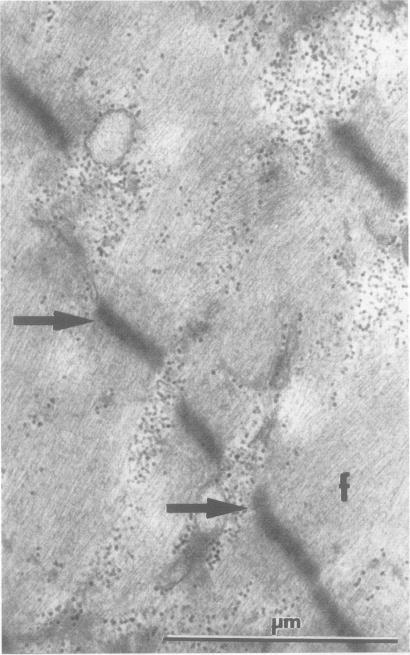

A 13 year old Greek girl with myasthenia gravis developed widespread muscle paralysis and atrophy after large parenteral doses of corticosteroids (5.48 g methylprednisolone). An electromyogram showed myopathy, creatine kinase concentration below normal, and a muscle biopsy showed severe myopathy with selective loss of the thick filaments (myosin). Previous reports of myopathy associated with large steroid doses have mostly been in patients who were also receiving non-depolarising neuromuscular blocking drugs. This patient is unique in that severe myopathy was associated with neuromuscular blockade caused by antibodies to acetylcholine receptors. The findings in this case suggest that high doses of parenteral corticosteroids in patients with myasthenia gravis may be dangerous and that blocking the neuromuscular junction with drugs or antibodies predisposes skeletal muscles to the injurious effects of corticosteroids.